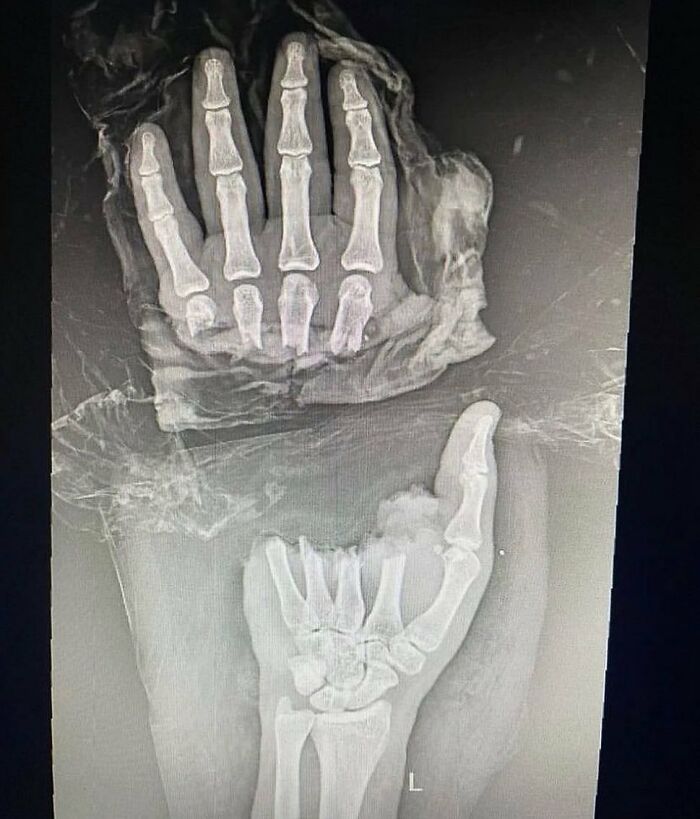

Guy Comes In With Amputation Of The Distal Half Of The Hand Resulting In Complete Separation Of Four Fingers At The Level Of Metacarpals

What do you think caused this injury?

Let your mind go wild on this one.

A. Machete attack

B. Chainsaw

C. Motorcycle crash

D. Manual meat slicer

E. Bear attack

F. Hydraulic press cutting machine

Edit: Answer - B!

Patient presented with traumatic amputation of the distal half of the hand following a work-related chainsaw accident. Full detachment of all four fingers at the metacarpal level.

Obviously, urgent medical evaluation and surgical intervention is needed, but first, let's just do an x-ray to see if it's broken, just to make sure.